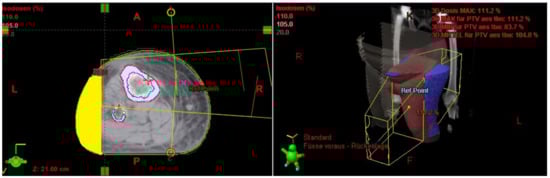

The Lymph-Sparing Quotient

Use of the Lymph-Sparing Quotient